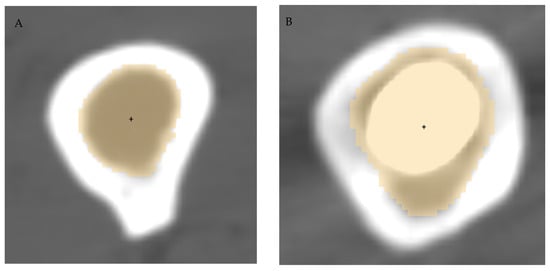

Figure 2. Segmentation of the femur canal (yellow shading) and identification of canal centroid (black dot) in the native side (A) and in the prosthetic side (B).

The radius of curvature was calculated at three levels of the femur, namely 10 (distal), 20 (middle) and 30 (proximal) cm above the reference axial plane, as well as for the whole femur. To measure the center of the medullary canal at each level, the level tracing method was used on the inner side of the medullary canal, with possible manual cleaning. Canal centroid was calculated as the geometric center of the level segmentation (Figure 2) using Matlab® (version R2019b, The MathWorks Inc, Natick, MA, USA).